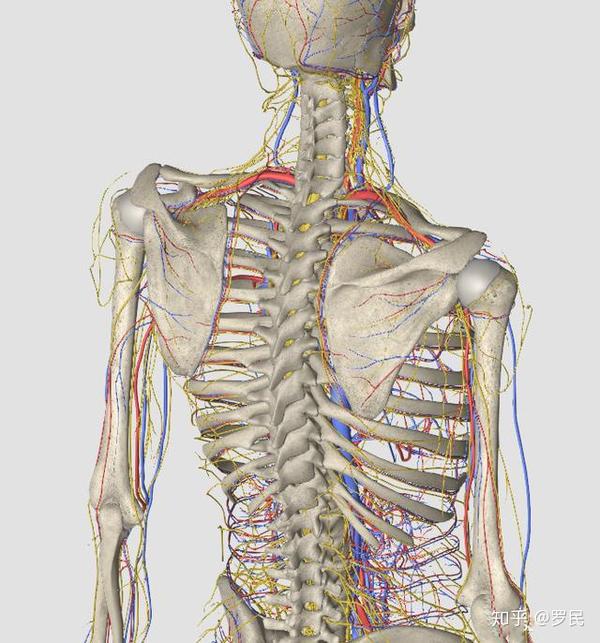

治疗手麻木手指麻木药活血通络颈椎压迫神经手麻脚麻专用贴膏神器 ¥ 150 颈椎贴颈椎病脖子痛头晕手麻去掉膏药贴消除富贵包专用神器正品Jun 21, 18 · 颈椎病压迫神经引起手麻怎么办:1、建议至大医院脊柱外科门诊,完善相关检查颈椎正侧位片,颈椎mri,明确颈椎病神经压迫的程度。 2、根据检查结果判断行?Mar 23, 21 · 其实颈椎病导致的手麻有其独特性,一起跟着空军军医大学唐都医院神经外科脊柱组李维新主任来了解下吧。 微信视频预览查看 颈椎病压迫所引发的手麻,有什么特点呢? 颈椎病引起的手麻有一个特点就是,在早期像一个树状的分布。

Aug 30, · 其中含有的羌活、葛根、威灵仙,抗炎镇痛效果比较好,能减轻缺血造成的头晕手麻,而川芎、丹参等有很强的活血和促进血液循环的作用,对治愈和缓解颈椎病引起的供血不足,缓解交感神经刺激引起的头晕效果显著;May 06, 21 · 颈椎病中最常见的一种类型是神经根型颈椎病,这类病人的常见表现就是手麻等上肢症状。简单来说,神经根型颈椎病是由于各种原因压迫颈神经根导致的,而人体一共有8对颈神经,它们分别支配着头部和上肢的运动、感觉等等,当不同颈神经根受压时,就会Jun 19, 19 · 颈椎压迫神经导致手臂和手麻,怎么治疗呢? 4;

Jul 22, 19 · 福州看颈椎压迫神经引起手麻哪家好?手机、电脑的普遍应用,产生了一个新名词:低头族。颈椎是承载人体头颅重量并连接躯干与头颅的重要位置,主要由颈椎骨质结构等构成,内有传达大脑对肢体指令的脊髓和神经走行。颈椎病对人体的造成的主要危害便是压迫脊髓或(和)神经。Sep 01, 15 · 颈椎压迫神经引起手麻怎么办 临床上对于神经压迫造成的手麻往往采用保守治疗的方法。 常见的保守治疗方法主要包括药物缓解、推拿按摩、牵引治疗、针灸疗法、理疗法等。 药物缓解:一般急性期选择一些常用神经抑制类药物、镇静剂、维生素之类的药物,对患者的症状有一定的缓解功效;如果手麻病史较长较为严重可以使用安颈贴之类的药物治疗,多是由活血化瘀Oct 14, 13 · 手麻便是神经根型颈椎病的症状之一,当人步入中年之后,随着年龄的增长,一些器官往往会发生退行性变,当颈椎间盘发生退行性变后,往往会导致颈椎间盘突出或颈椎关节增生和肥大,这些突出的颈椎间盘或增生的关节一旦压迫临近的颈神经根时,便会引发